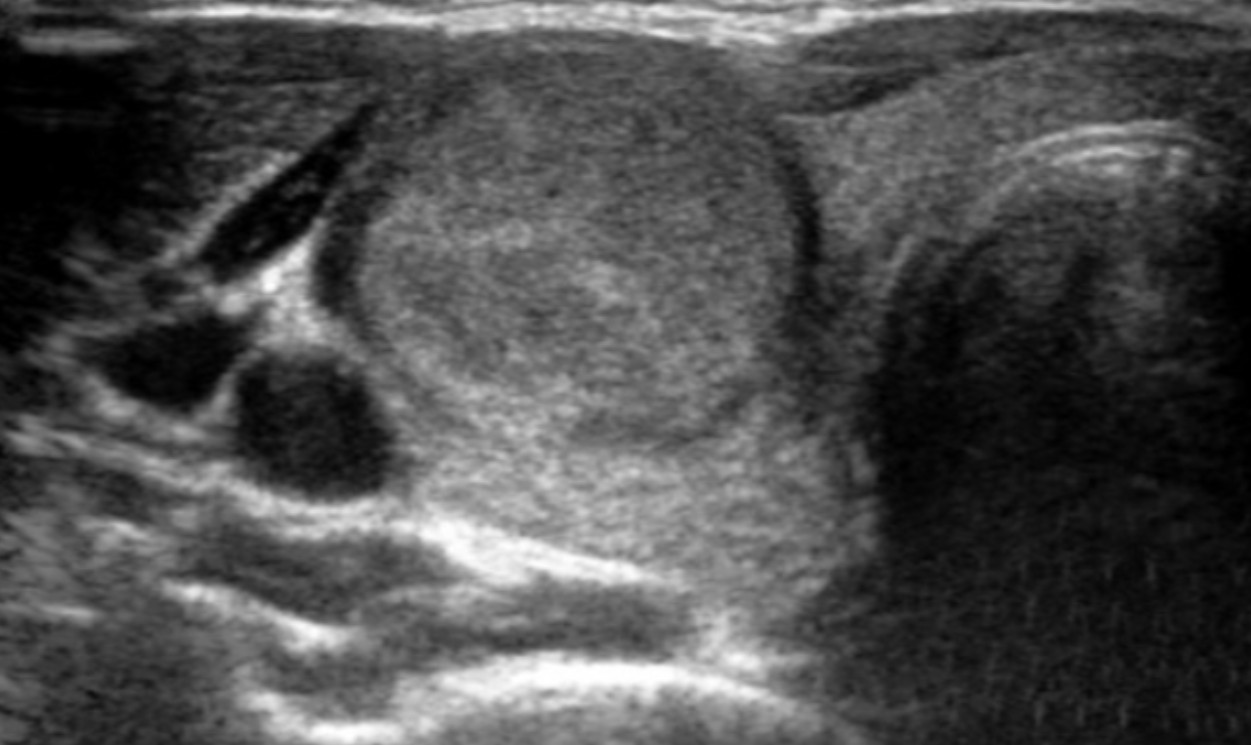

Se realizó ultrasonido con toma de biopsia por aspiración con aguja fina.

Se encontró nódulo intratiroideo de 4 cm de diámetro, TIRADS 3.